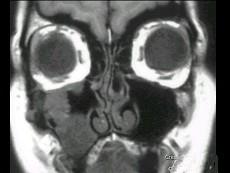

女性,50岁,右鼻塞、脓涕3个月,CT、MRI检查如图所示,请选择正确的答案 ( )

• A.右侧上颌窦积液

• B.右侧上颌窦腺样囊性癌

• C.右侧上颌窦粘膜下囊肿

• D.右侧上颌窦黏液腺瘤

• E.右侧上颌窦黏液囊肿

答案: B